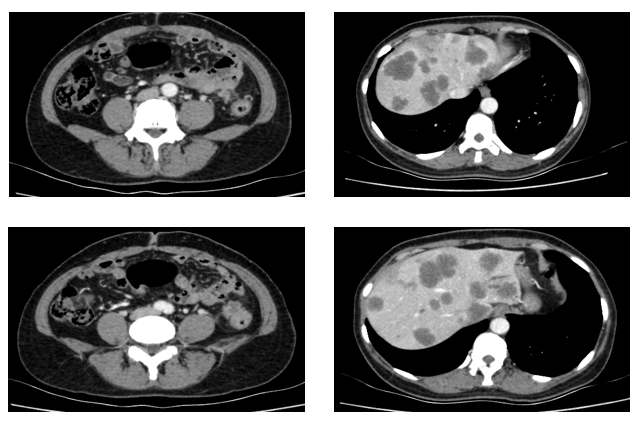

患者为51岁女性,因“间断腹痛半年余,进行性加重1月”于2021年3月就诊于我院结直肠外科。入院时胸全腹部CT(2021-3-29)提示:降结肠远端增厚,肝内多发占位,肺内多发小结节,考虑转移。肠镜检查:在距肛门28公分处,管腔狭窄,内镜不能通过。病理提示:腺癌。

于2021.04.17行“FOLFOX6”方案化疗1周期,行“奥沙利铂”化疗时,出现严重过敏。因患者基因状态为RAS,BRAF野生型,第2周期始给予“FOLFIRI+西妥昔单抗”,在治疗过程中,肿瘤标志物持续下降,影像学也显示肝脏病灶明显缩小。疗效评价PR,在2021-09-25在局麻DSA下行“肝动脉造影并化疗灌注栓塞术”。

于2021-12-03、2021-12-27给予伊尼妥单抗+吡咯替尼方案治疗2周期。2022.1.19始给予患者伊尼妥单抗+吡咯替尼+替雷利珠单抗治疗,两周期,四周期时的疗效评估可以看到,肺上病灶明显缩小,甚至有的病灶消失,肿瘤标志物也在持续下降。

2022-09-07至2023-01-03院外使用DS-8201治疗5周期。2周期后疗效评价:PR。CT示:腹膜后淋巴结较前部分缩小;双肺多发转移灶较前缩小。